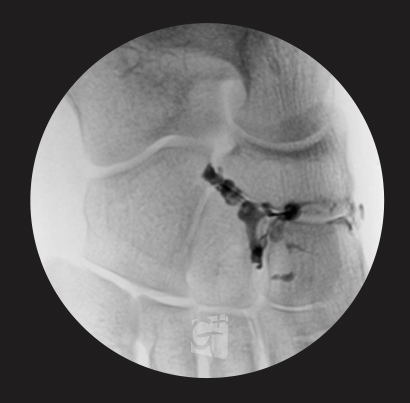

손목 치료

손목 관절 주변 염증, 힘줄염 등

염증부위에 주사 시술 -